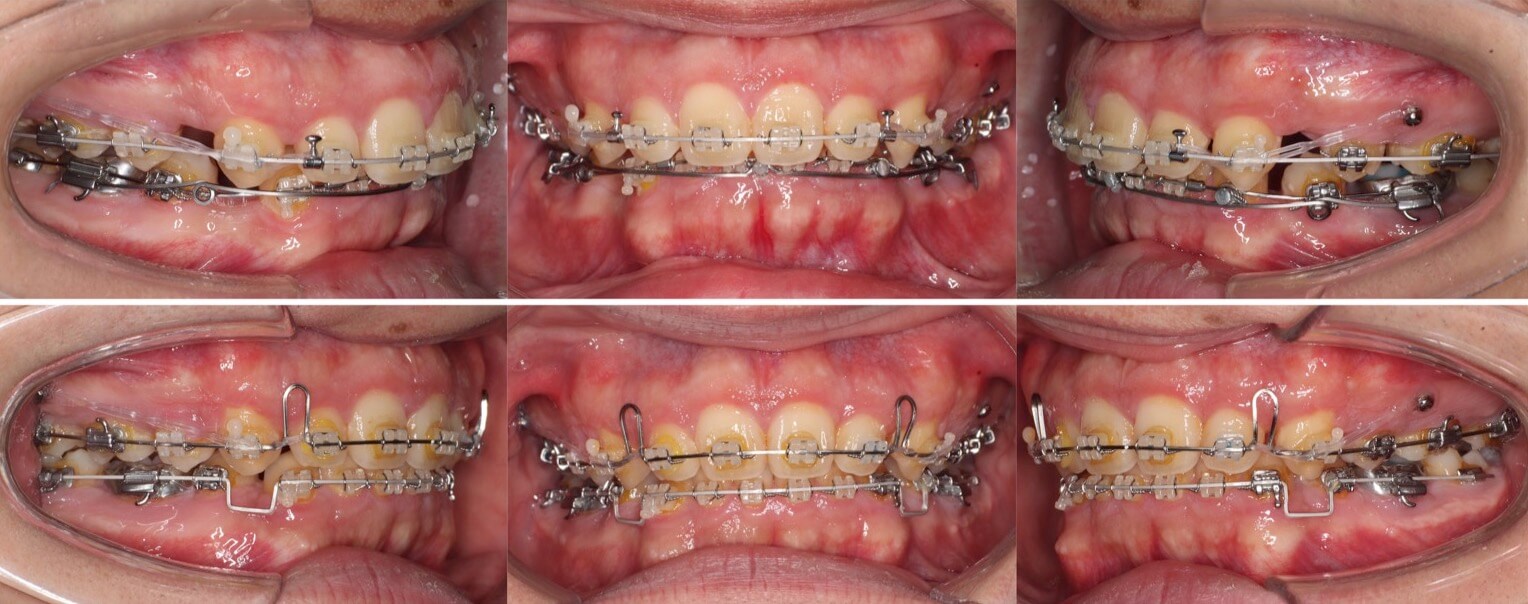

20代女性・唇側矯正装置・2本抜歯

重度の過蓋咬合であったため、唇側ワイヤー矯正装置とアンカースクリューにより、先に上の前歯の圧下(歯茎方向への移動)を行なった後に、ゆっくりと抜歯空隙を閉鎖しました。このように過蓋咬合では前歯に植立するアンカースクリューがあった方が治療が効率的に進みます。

<症例概要>

主訴:前歯の突出と噛み合わせ

年齢・性別:20代女性

住まい:東京都練馬区

症状:過蓋咬合・上顎前突

治療方針:上顎前歯の圧下・抜歯空隙の閉鎖

治療装置:唇側矯正装置

固定装置:歯科矯正用アンカースクリュー(上唇側x2)

抜歯:上左右第一小臼歯(計2本)

治療期間:2年6か月

リテーナー:下フィックスタイプ+上下プレートタイプ

治療費用:968,000(税込)

代表的副作用:痛み・治療後の後戻り・歯根吸収・歯髄壊死・歯肉退縮

▶︎その他の副作用